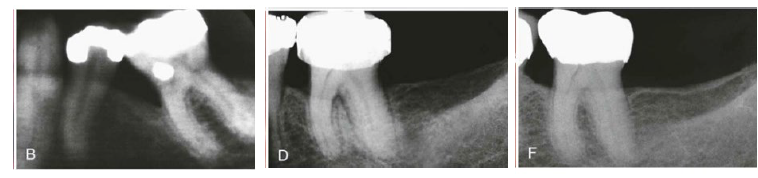

Q